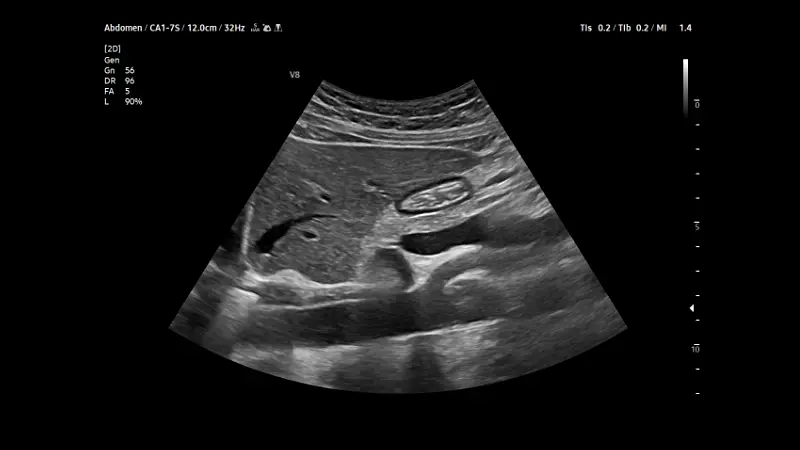

Inhalte sind wichtige allgemeine Grundlagen der Ultraschalldiagnostik und die Einführung in die sonografische Organdiagnostik in Akutsituationen (Herz, Thorax und Abdomen). Dieser Kurs bildet ebenfalls die Basis für die Zertifizierung Sonographie im Rettungsdienst.

In diesem Kurs werden systematisch Untersuchungs-techniken zur erweiterten sonografischen Organ-diagnostik (Herz, Thorax, Abdomen, Gefäße) in Akutsituationen mit den für Akutmediziner wichtigen Pathologien vermittelt.

In diesem Kurs werden die im Grundkurs vermittelten Techniken um die wichtigsten Messverfahren erweitert um Pathologien reproduzierbar zu detektieren und quantifizieren.